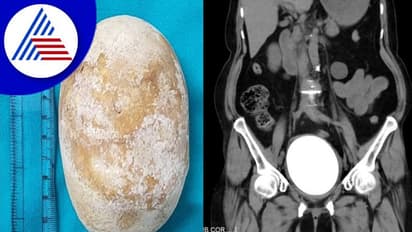

ಉಡುಪಿ (ನ.25): ಮಣಿಪಾಲದ ಕಸ್ತೂರ್ಬಾ ಆಸ್ಪತ್ರೆಯಲ್ಲಿನ ಮೂತ್ರಶಾಸ್ತ್ರಜ್ಞರ ತಂಡವು ಅತಿದೊಡ್ಡ ಮೂತ್ರಕೋಶದ ಕಲ್ಲು ಯಶಸ್ವಿಯಾಗಿ ತೆಗೆದು ಹಾಕಿದೆ. 60 ವರ್ಷ ವಯಸ್ಸಿನ ಮಹಿಳೆ ಕಳೆದ ಆರು ವರ್ಷಗಳಿಂದ ಉರಿ ಮೂತ್ರ ದೂರುಗಳೊಂದಿಗೆ ಸ್ಥಳೀಯ ಆಸ್ಪತ್ರೆಗೆ ಭೇಟಿ ನೀಡುತ್ತಿದ್ದರು. ಈ ರೋಗಲಕ್ಷಣಗಳ ಪ್ರತಿ ಭೇಟಿಯಲ್ಲಿ ಮೂತ್ರನಾಳದ ಸೋಂಕಿಗೆ ಪ್ರಾಯೋಗಿಕವಾಗಿ ಚಿಕಿತ್ಸೆ ನೀಡಲಾಗಿತ್ತು. ಇತ್ತೀಚೆಗೆ ಕಸ್ತೂರ್ಬಾ ವೈದ್ಯಕೀಯ ಕಾಲೇಜು ಮತ್ತು ಆಸ್ಪತ್ರೆಗೆ ಭೇಟಿ ನೀಡಿದ್ದರು. ರೋಗಿಗೆ ಸರಳ ಸಿಟಿ ಸ್ಕ್ಯಾನ್ ಮಾಡಲಾಯಿತು.

ಇದು ಸಂಪೂರ್ಣ ಮೂತ್ರಕೋಶವನ್ನು ಆಕ್ರಮಿಸಿಕೊಂಡಿರುವ ಗಮನಾರ್ಹವಾದ ವಸ್ತು ಇರುವುದನ್ನು ಬಹಿರಂಗಪಡಿಸಿತು. ಮೂತ್ರಶಾಸ್ತ್ರ ವಿಭಾಗದ ಪ್ರಾಧ್ಯಾಪಕ ಮತ್ತು ಉಪ ವೈದ್ಯಕೀಯ ಅಧೀಕ್ಷಕರಾದ ಡಾ ಪದ್ಮರಾಜ್ ಹೆಗ್ಡೆ ಅವರ ಮಾರ್ಗದರ್ಶನದಲ್ಲಿ ಈ ವಸ್ತುವನ್ನು ಹೊರತೆಗೆದಾಗ ಅಚ್ಚರಿ ಕಾದಿತ್ತು. ಬರೋಬ್ಬರಿ, 11.5 x 7.5 ಸೆಂ.ಮೀ ಅಳತೆಯ 672 ಗ್ರಾಂ ತೂಕದ ಮೂತ್ರಕೋಶದ ಕಲ್ಲನ್ನು ಡಾ.ಅಂಶುಮನ್, ಡಾ.ಕಾಶಿ ವಿಶ್ವನಾಥ್, ಡಾ.ನಿಶಾ ಡಾ ವಿವೇಕ್ ಪೈ ಮತ್ತು ಡಾ ಕೃಷ್ಣ ಅವರ ತಂಡವು ತೆರೆದ ಸಿಸ್ಟೊಲಿಥೊಟಮಿ ಶಸ್ತ್ರಚಿಕಿತ್ಸೆ ಮೂಲಕ ಹೊರ ತೆಗೆದರು. ಎರಡನೇ ದಿನ ರೋಗಿಯನ್ನು ಆಸ್ಪತ್ರೆಯಿಂದ ಬಿಡುಗಡೆ ಮಾಡಲಾಯಿತು.

ಅಲ್ಟ್ರಾಸೋನೋಗ್ರಫಿ ಅಥವಾ ಎಕ್ಸ್-ರೇನಂತಹ ಆರೋಗ್ಯ ಸೌಲಭ್ಯಗಳನ್ನು ಹೊಂದಿರುವ ಗ್ರಾಮೀಣ ಪ್ರದೇಶಗಳಲ್ಲಿ ರೋಗನಿರ್ಣಯವನ್ನು ಮಾಡುವುದು ಸವಾಲಿನ ಸಂಗತಿಯಾಗಿದೆ. ನಮ್ಮ ಜ್ಞಾನದ ಪ್ರಕಾರ ಆರೋಗ್ಯವಂತ ವಯಸ್ಕ ಮಹಿಳೆಯಲ್ಲಿ 672 ಗ್ರಾಂ ತೂಕದ ದೈತ್ಯ ಮೂತ್ರಕೋಶದ ಕಲ್ಲು ಪ್ರಕರಣವು, ನಮ್ಮ ಜ್ಞಾನದ ಪ್ರಕಾರ ಇದು ವಿಶ್ವದಲ್ಲಿ ವರದಿಯಾಗಿರುವ ಮಹಿಳಾ ರೋಗಿಯಲ್ಲಿನ ಅತಿ ದೊಡ್ಡ ಮೂತ್ರಕೋಶದ ಕಲ್ಲು.

ಇಲ್ಲಿಯವರೆಗೆ ವರದಿಯಾದ ಅತಿದೊಡ್ಡ ಮೂತ್ರಕೋಶದ ಕಲ್ಲು ಮುಂಬೈನ ಕೆಇಎಂ ಆಸ್ಪತ್ರೆಯಿಂದ, ಅದು 528 ಗ್ರಾಂ ತೂಕವಿತ್ತು ಎಂದು ವೈದ್ಯರ ತಂಡ ತಿಳಿಸಿದೆ. ಅಪರೂಪದ ಕ್ಲಿಷ್ಟಕರ ಶಸ್ತ್ರಚಿಕಿತ್ಸಾ ಪ್ರಕ್ರಿಯೆಯನ್ನು ಯಶಸ್ವಿಯಾಗಿ ನಡೆಸಿದ ತಂಡವನ್ನು ಮಾಹೆ ಮಣಿಪಾಲದ ಭೋದನಾ ಆಸ್ಪತ್ರೆಗಳ ಮುಖ್ಯ ನಿರ್ವಹಣಾಧಿಕಾರಿ ಡಾ ಆನಂದ್ ವೇಣುಗೋಪಾಲ್ ಮತ್ತು ವೈದ್ಯಕೀಯ ಅಧೀಕ್ಷಕ ಡಾ ಅವಿನಾಶ್ ಶೆಟ್ಟಿ ಅಭಿನಂದಿಸಿದ್ದಾರೆ.